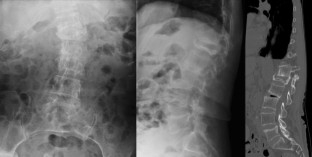

Osteoporotic vertebral fracture (OVF) with nonunion or neurological deficit may be a candidate for surgical treatment. However, some patients do not show improvement as expected. Therefore, we conducted a nationwide multicenter study to determine the predictors for postoperative poor activity of daily living (ADL) in patients with OVF.

The frequency of poor ADL at final follow-up period was 9.1%. In univariate analysis, preoperative neurological deficit (OR, 4.1; 95% CI, 1.8–10.3; P < 0.001), perioperative complication (OR, 3.4; P = 0.006), absence of preoperative bone-modifying agent (BMA) administration (OR, 2.7; P = 0.03), and absence of postoperative recombinant human parathyroid hormone (rPTH) administration (OR, 3.9; P = 0.006) were significantly associated. In multivariate analysis, preoperative neurological deficit (OR, 4.6; P < 0.001), perioperative complication (OR, 3.4; P = 0.01), and absence of postoperative rPTH administration (OR, 3.9; P = 0.02) showed statistical significance.

Preoperative neurological deficit, perioperative complication, and absence of postoperative rPTH administration were considered as predictors for postoperative poor ADL in patients with OVF. Neurological deficits and complications are often inevitable factors; therefore, rPTH is an important option for postoperative treatment for OVF.